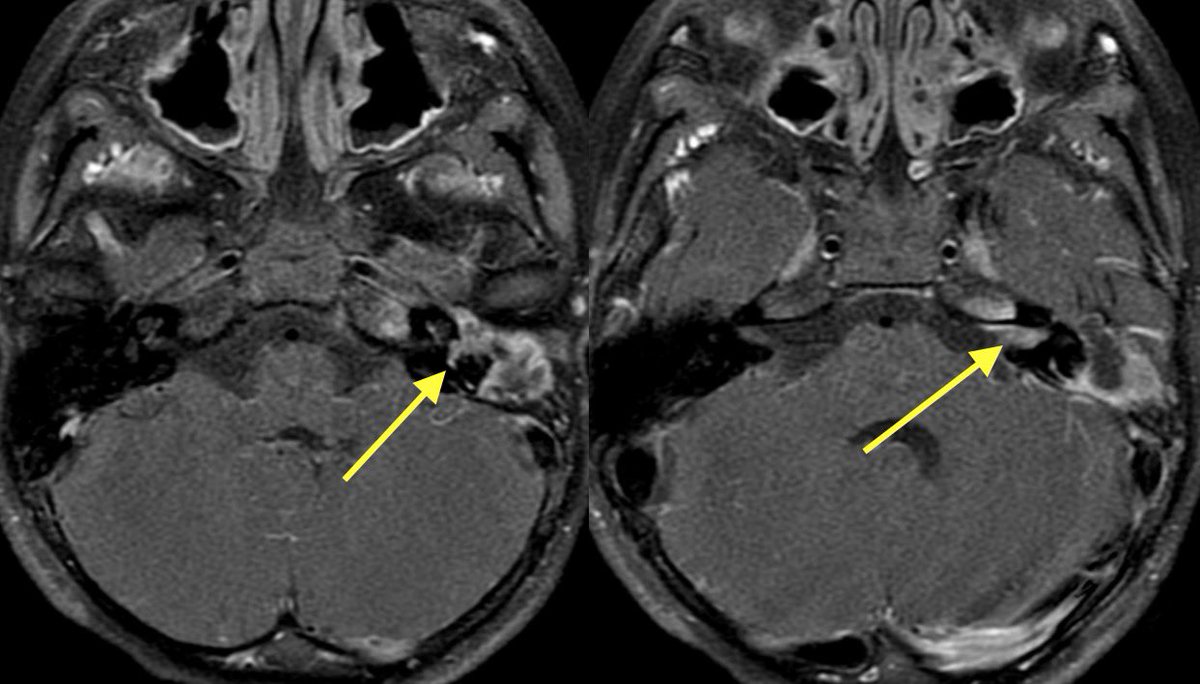

2️⃣However, additional restriction, enhancement, and loss of normal CSF signal in the left IAC was highly suggestive of suppurative Labyrinthitis

Cholesteatoma with superimposed infection was also complicated by meningitis (seen best at quadrigeminal plate cistern), ventriculitis, skull base osteomyelitis (petrous apicitis) and probably some other itisis that I’m forgetting

Patient developed acute left sided weakness and thus stroke code was activated

💡 Meningitis is a risk factor for stroke

💡 Meningitis can induce vasospasm from arterial irritation (just like SAH)

💡 Can also cause infectious vasculitis

MR shows the extent of the core infarct involving the right BG and MCA-ACA border zone (watershed)